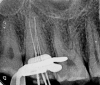

This report illustrates a rare case of a geminated maxillary right second molar tooth using CBCT in a 23-year-old man with severe pain. Nonsurgical endodontic treatment was performed, which gave rise to an asymptomatic tooth at the 12-month follow-up.